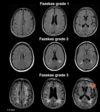

Which scale is used to quantify the amount of white matter T2 hyperintense lesions usually attributed to chronic small vessel ischaemia? 1 - Fazekas scale 2 - Wells score 3 - Dukes score 4 - McDonald score

1 - Fazekas scale